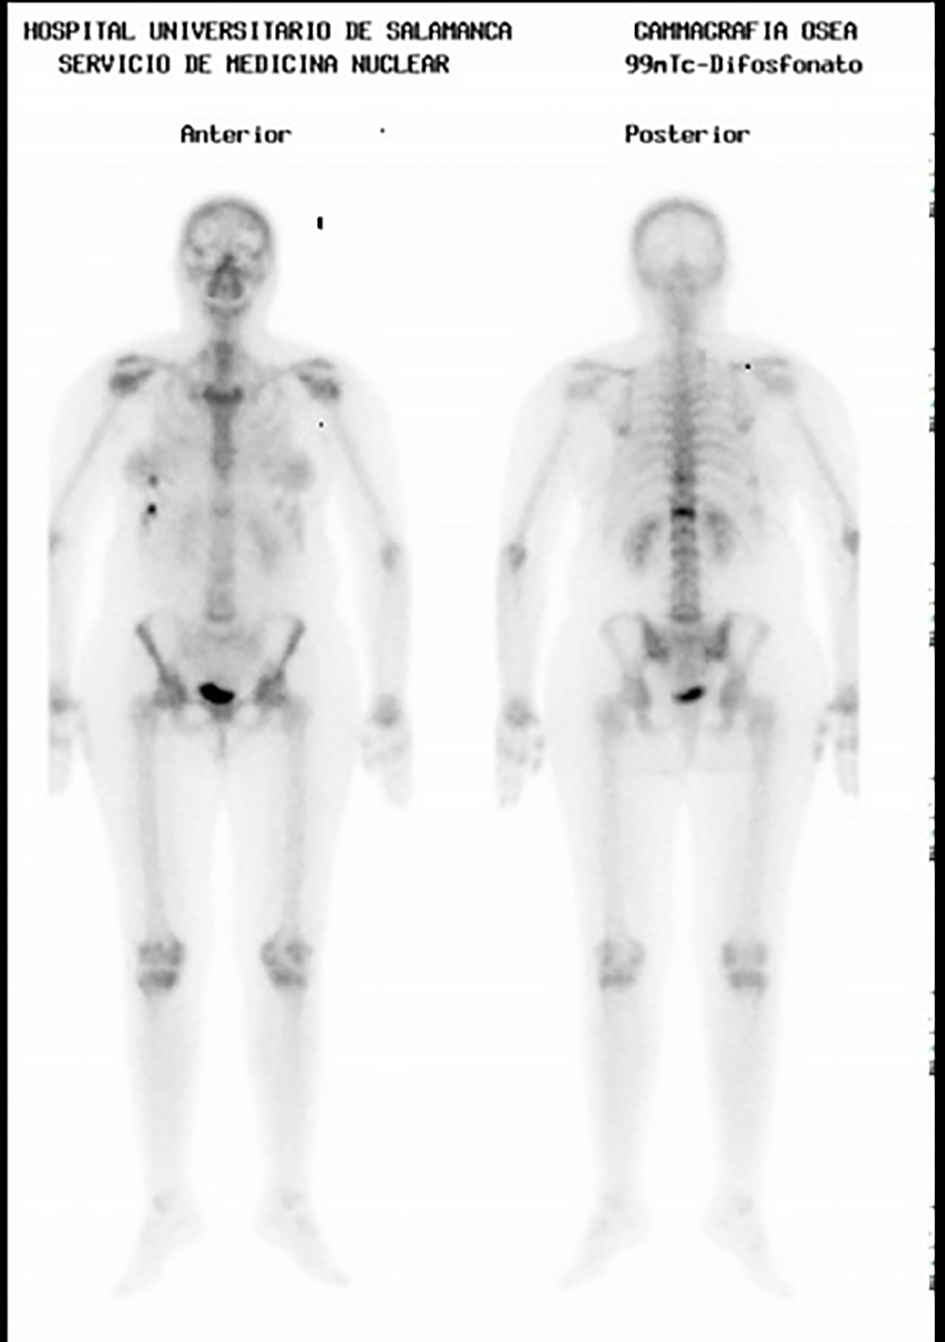

![]() Click for large image | Figure 3. Bone scintigraphy with technetium 99: enhancement of the tracer on the knees, ankles, tarsal and metatarsal bones. |

The control bone scintigraphy which was performed 3 months later detected a lower enhancement of technetium 99 tracer (Fig. 4), as well as normal figures for Ca and vitamin D in the analytical tests.

![]() Click for large image | Figure 4. Bone scintigraphy with technetium 99: decreased enhancement of the tracer. |